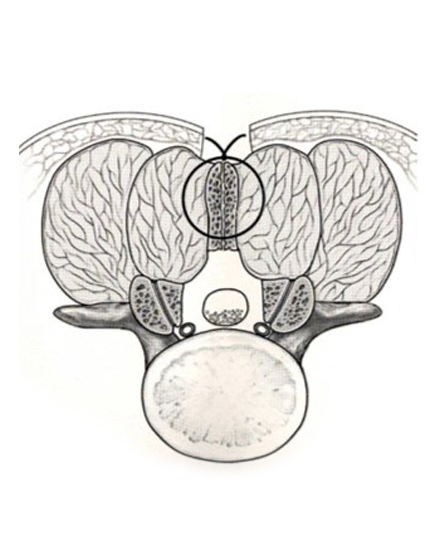

腰椎棘突起縦割式椎弓切除術

適応となる疾患:腰部脊柱管狭窄症、腰椎変性すべり症など

腰椎後方(背中)から椎弓、肥厚した黄色靭帯を切除し、硬膜管(馬尾神経の通っている管)の圧迫を解除します。棘突起を縦割することで腰背筋を骨から切離せず温存して、余分な組織のみ切除する低侵襲な手術を行います。従来の手術に比べ、術後の腰痛が軽度です。手術時間は1時間くらいで翌日から歩行が許可されます。入院期間は通常10~14日ぐらいになります。